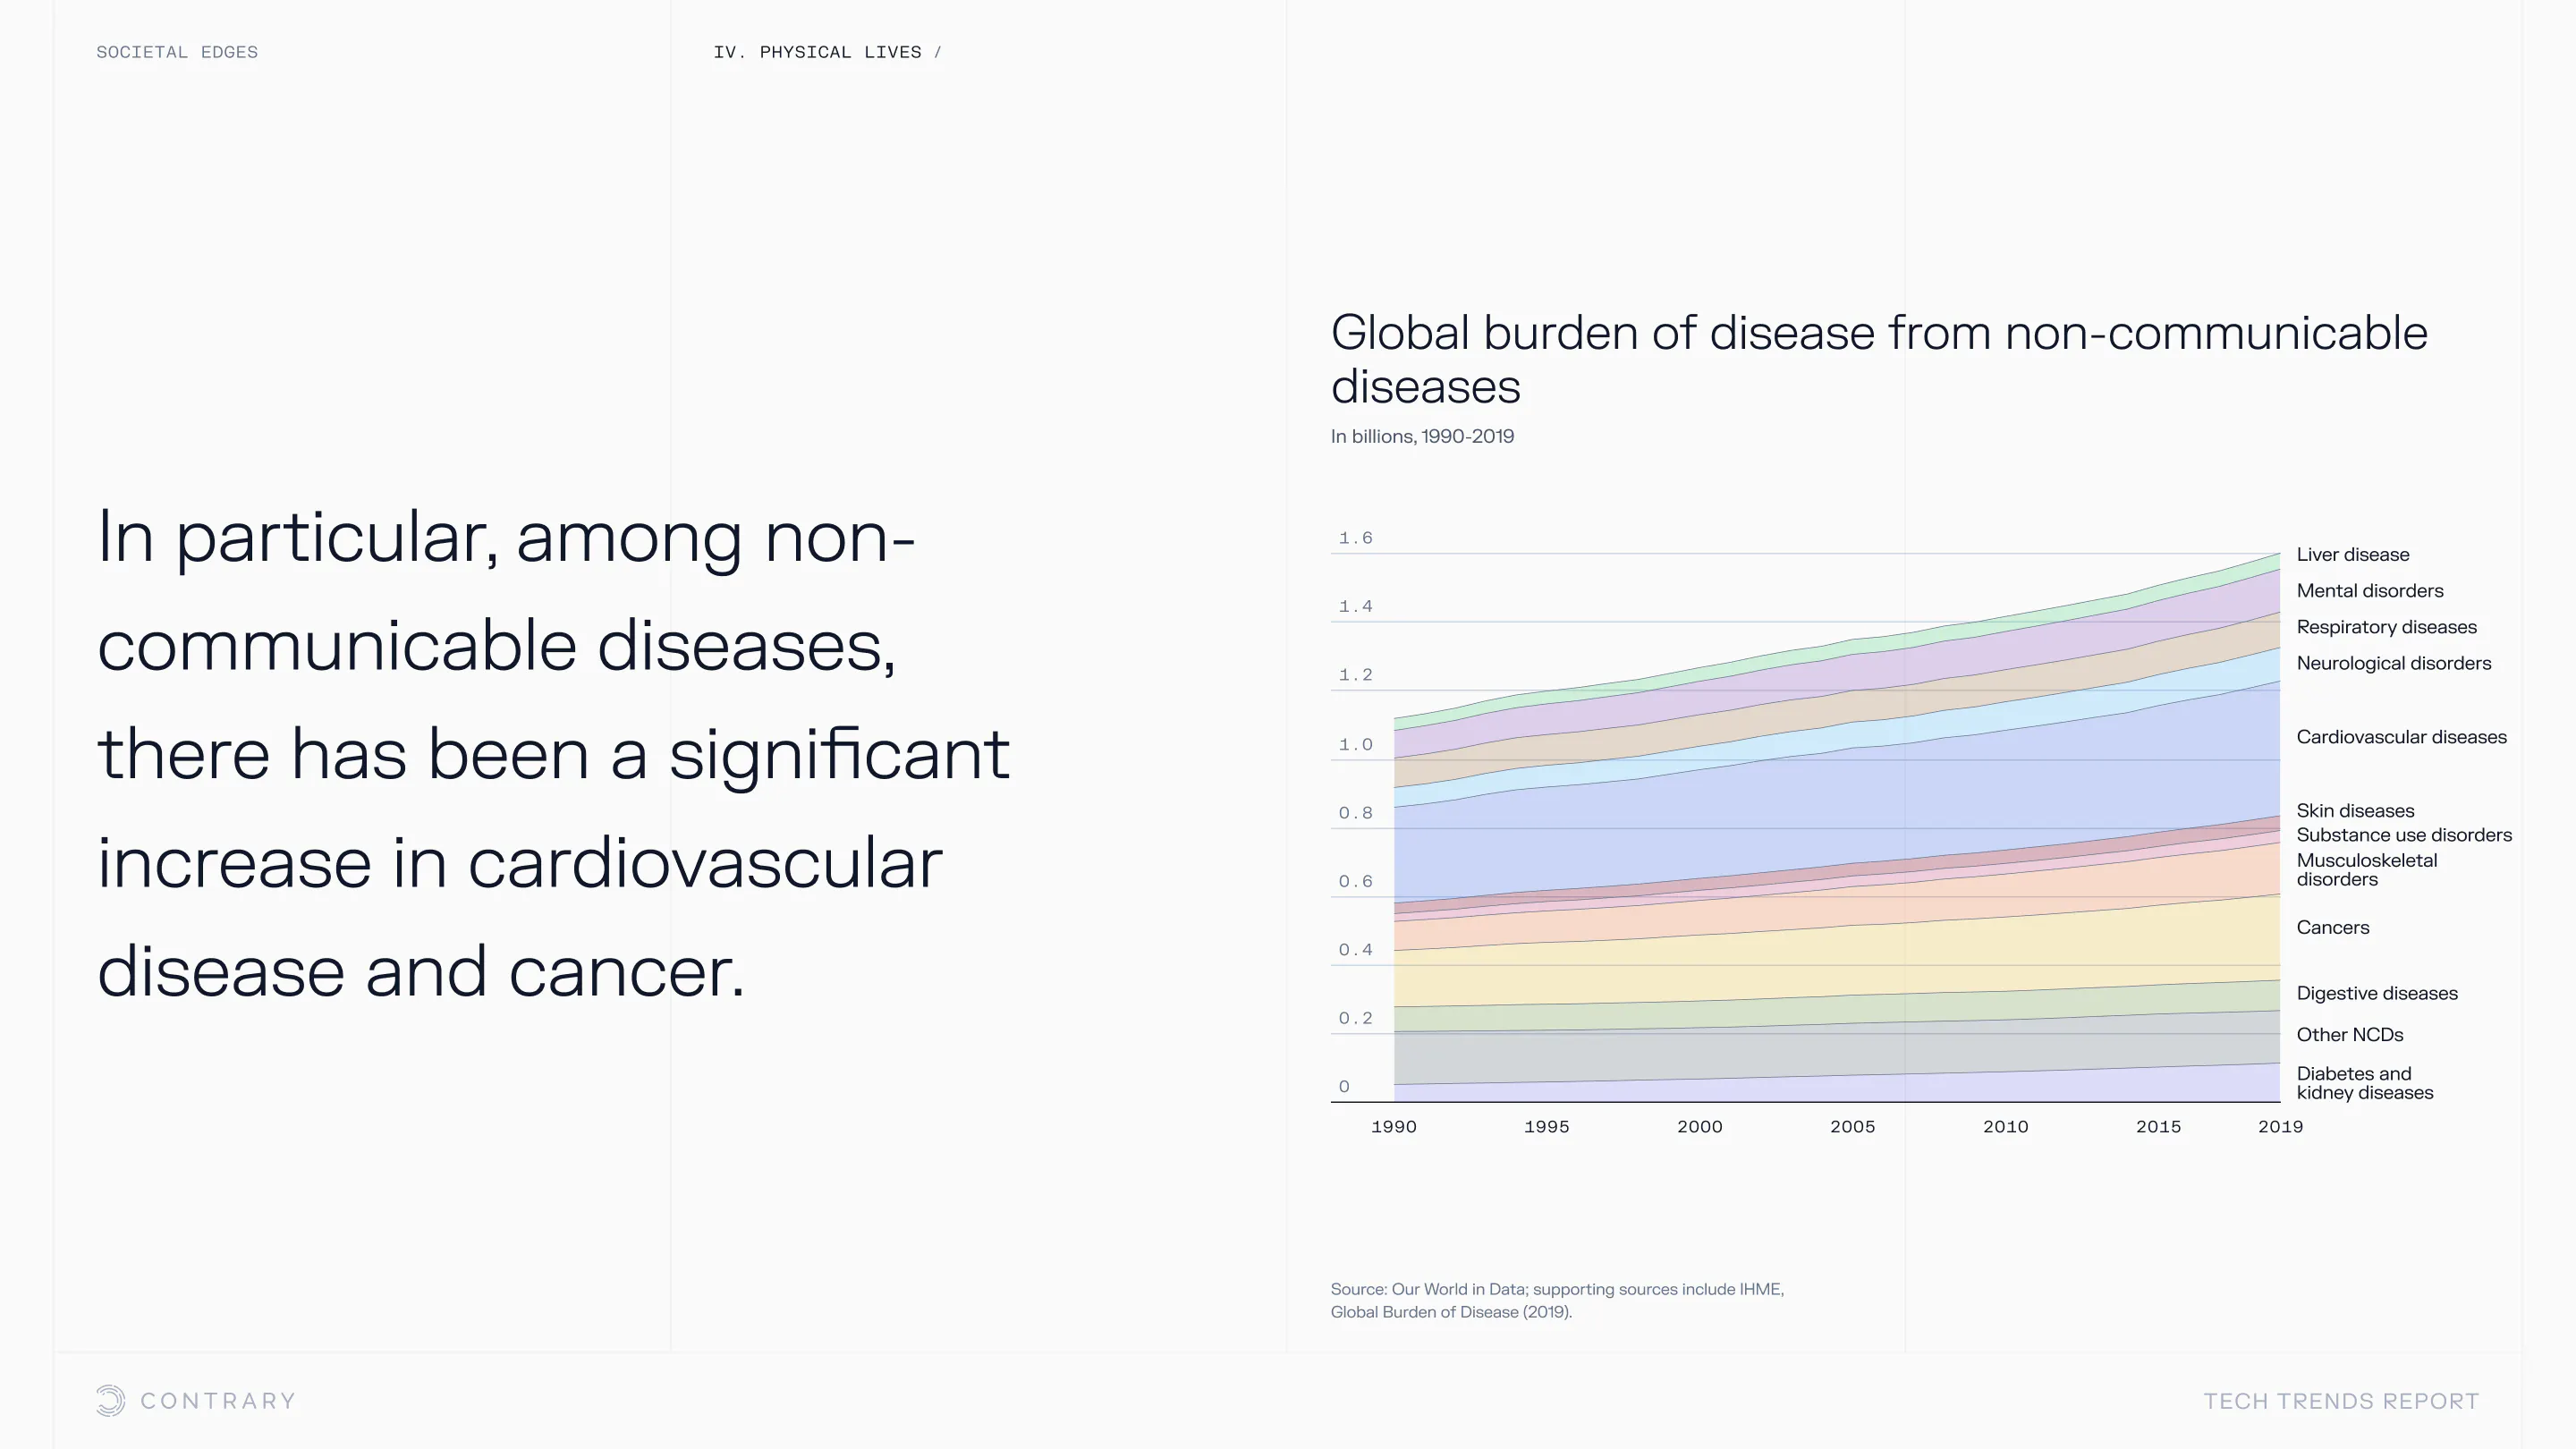

An aging population is bringing up a range of increased concerns, from mental health to disease control. Obesity and gastrointestinal cancers are plaguing younger generations. The cutting edge is tackling a system that has unhealthiness woven into it.